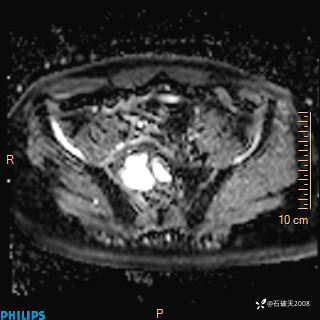

2023年3月份MRI影像

增强轴位